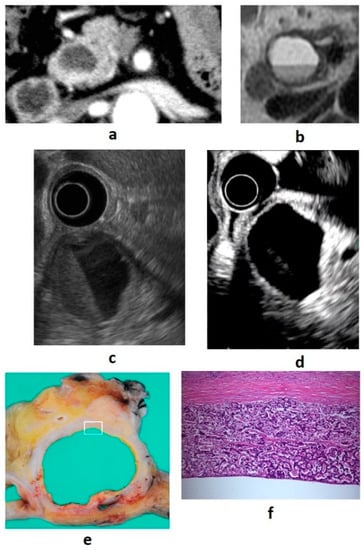

8.1. Cystic Degeneration

The most common cause of cystic degeneration is tumor bleeding, whereas tumor necrosis is rarely the cause. Cystic degeneration is mostly observed in well-differentiated PNENs. The frequency is 10–17% of all PNENs, and the larger the tumor, the higher the rate of cystic degeneration [31]. Gaujoux et al. found no association between cystic degeneration and tumor malignancy [31]. The biological behavior of cystic PNENs is somewhat less aggressive than that of solid PNENs [32,33]. Cystic degeneration is visualized as a low absorption area on contrast CT and is recognized as a nonechoic area on B-mode EUS and as an avascular area on CE-EUS. If the cysts become larger, the imaging findings will be similar to those of serous cystic neoplasms, and differentiation is necessary [34]. In EUS diagnosis, it is important to identify the solid tumor part of the cyst margin as a wall thickening or protrusion. Examples of cystic PNEN images from our department are shown in Figure 3.

Figure 3. (a) Contrast-enhanced computed tomography (CT): a cystic lesion is seen on the pancreatic head. (b) Magnetic resonance imaging: fluid–fluid level formation is shown. (c) B-mode endoscopic ultrasound (EUS): a cystic lesion with fluid–fluid level formation and a thickened wall is seen. (d) Contrast-enhanced EUS: the wall is hyperenhanced compared with the surrounding pancreatic parenchyma. (e,f) Resected specimen: neuroendocrine neoplasm G1 (100×).